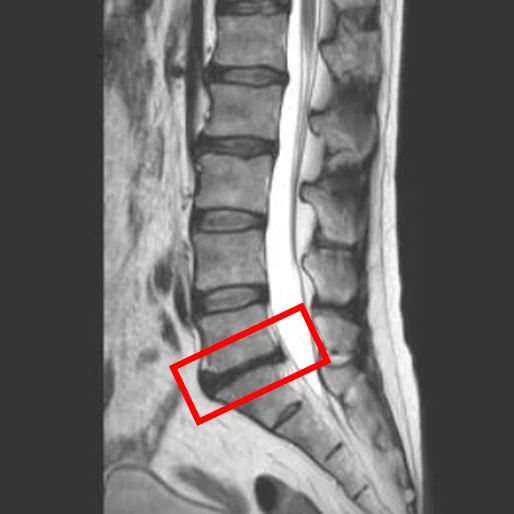

По данным МРТ и результатам осмотра пациента выявлена дегенерация межпозвоночных дисков L2/L3 и L5/S1, а также стеноз межпозвонковых отверстий L5/S1.